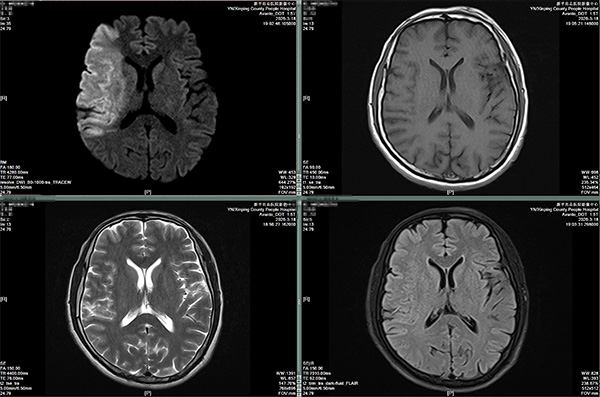

1.敏感如雷达。病变早期,哪怕器官形态还没发生变化,只要水分子运动异常,DWI就能第一时间发现信号,尤其对急性脑梗死,能快速捕捉急性病变,是急诊和早期诊断的关键工具,发病30分钟左右就能揪出病灶,为抢救争取黄金时间。

图一:超急性期脑梗死,普通磁共振检查系列没有发现病变,但DWI能快速捕捉到病变。